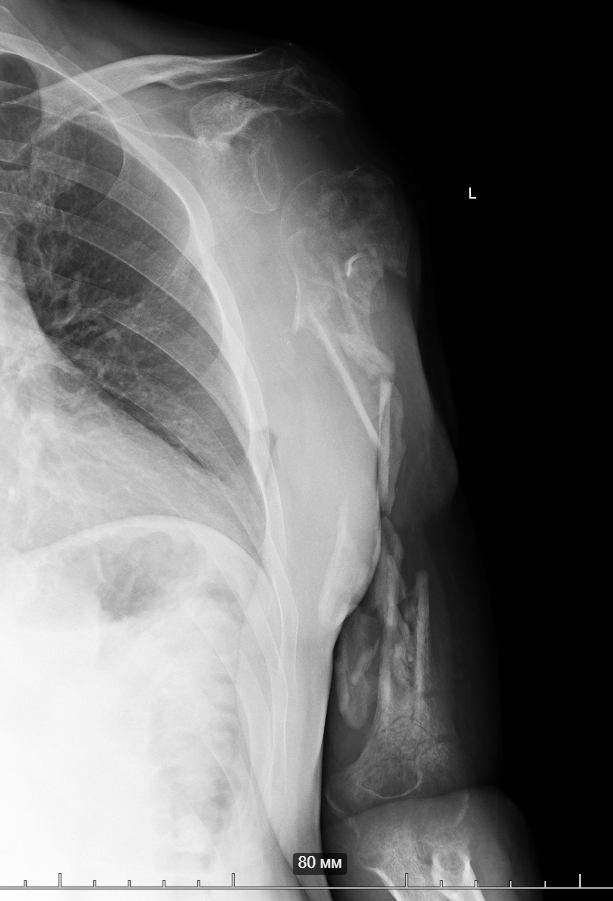

A soldier (now demobilized) sustained a blast injury in February of this year.

Six procedures were initially performed to begin the limb-salvage process for the arm (external fixation and wound debridement).

Despite the wound becoming infected with a “military” bacterium (American surgeons refer to this and Acinetobacter as the “Iraq bacteria” or “veterans’ disease”), Ukrainian doctors were able to manage the infection.

Simultaneously, several skin grafting procedures were carried out. One of Ukraine’s best plastic surgeons performed a thoracodorsal flap. The wounds have healed. The patient was transferred to us after 6 weeks of rehabilitation.

But the “Iraq bacterium” (named after the experience of wounded U.S. veterans) proved to be a particularly insidious microorganism.

So, together with Vasyl Parii and Denys Dolgush, instead of performing massive bone grafting immediately, we decided to stabilize the severely damaged humerus (see X-rays) with a plate using a minimally invasive approach — and took new tissue samples for culture. In peacetime and in case of a normal civilian injury (usually the main bacteria in such cases is Staphylococcus Aureus), we would do bone grafting simultaneously with internal fixation. But the presence of the “Iraqi bacteria” in early investigations does not allow this; the risk of severe complications is too high.